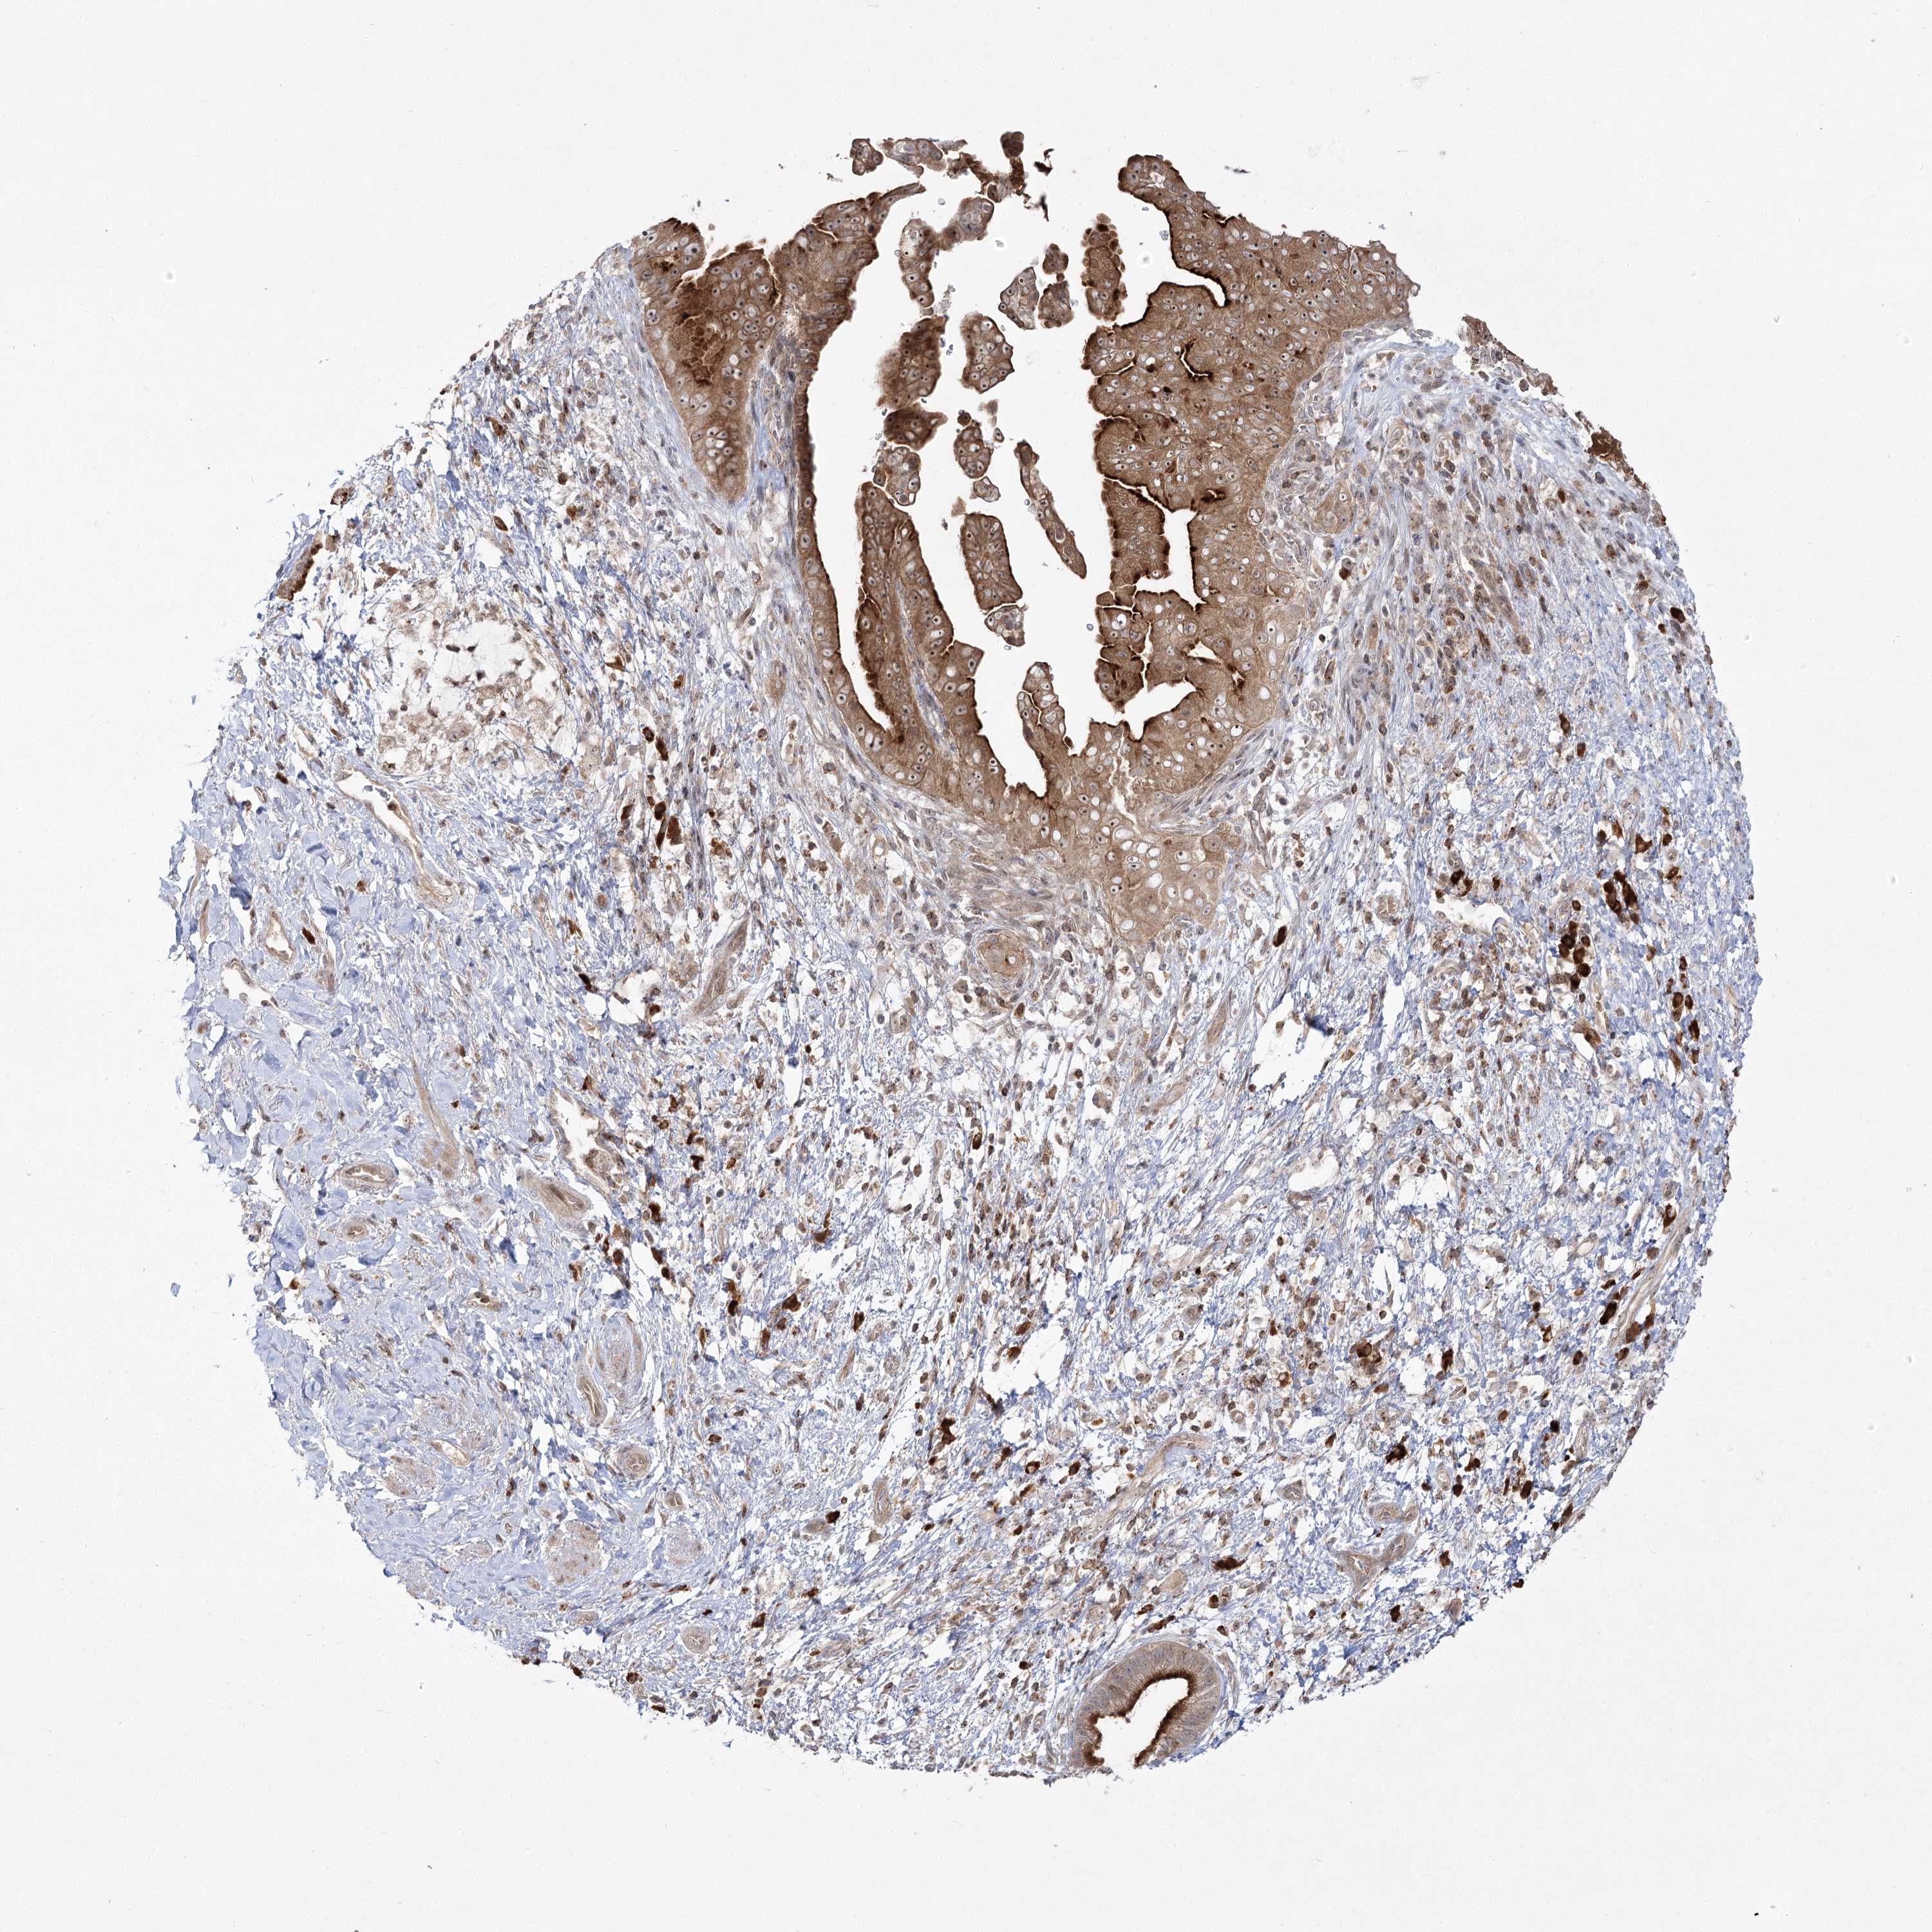

PANCREATIC CANCER - Protein expressioni

A mouse-over function shows sample information and annotation data. Click on an image to view it in a full screen mode. Samples can be filtered based on level of antibody staining by selecting one or several of the following categories: high, medium, low and not detected. The assay and annotation is described here.

Note that samples used for immunohistochemistry by the Human Protein Atlas do not correspond to samples in the TCGA dataset.

Antibody stainingi

Antibody staining in the annotated cell types in the current human tissue is reported as not detected, low, medium, or high, based on conventional immunohistochemistry profiling in selected tissues. This score is based on the combination of the staining intensity and fraction of stained cells.

Each image is clickable and will lead to virtual microscopy that enables deeper exploration of all samples and also displays staining intensity scores, fraction scores and subcellular localization as well as patient and tissue information for each sample.

Antibody HPA037825

Staining

High

Medium

Low

Not detected

Intensity

Strong

Moderate

Weak

Negative

Quantity

>75%

75%-25%

<25%

None

Location

Nuclear

Cytoplasmic/membranous

Cytoplasmic/membranous,nuclear

Adenocarcinoma, NOS